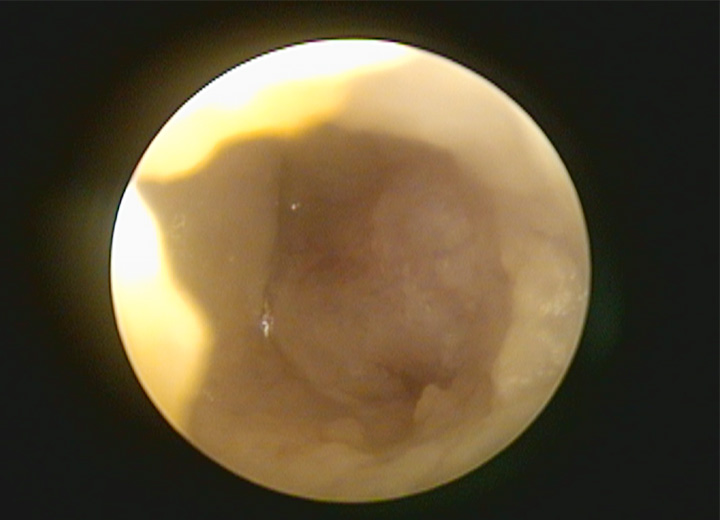

オトスコープ(耳内視鏡)検査

オトスコープは、耳鏡検査よりもより詳細に耳の内部を観察することができるカメラのような器具です。

オトスコープ検査により耳の中の炎症や異物をチェックし、外耳炎や鼓膜の先の中耳炎の診断が可能です。

オトスコープは耳の中を観察できるだけでなく、外耳や内耳の洗浄を行ったり、異物の除去や腫瘍の切除を行ったりと治療にも使用することができます。

耳鏡検査だけでは分からなかった情報を得るためにも、オトスコープ検査は有用ですね。

オトスコープは内視鏡の一種なので、検査に麻酔が必要だと思われる方もいますが、観察だけであれば無麻酔での実施が可能です。

猫の性格や耳の痛みによっては麻酔が必要になることもありますので、よく獣医師と相談しましょう。